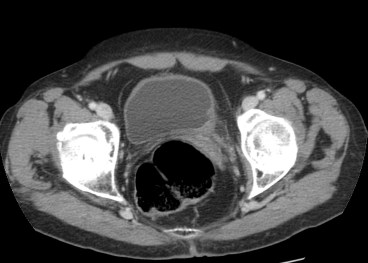

EXTENSIÓN:

Estadíos:

- T1: Invaden la lamina propia.

- T2: Invaden las capas superficiales del músculo.

- T2b: Invaden las capas profundas del músculo.

- T3a: Extensión perivesical microscópica.

- T3b: Extensión macroscópica.

- T4: Invaden órganos vecinos o la pared pélvica.

La realización de una uro-TC o un TC de vejiga tiene limitaciones a la hora de realizar la estadificación ya que no podemos distinguir el cáncer No músculo invasivo del que sí lo invade y, además, no podemos detectar mediante TC la invasión microscópica perivesicual del tumor que constituye el estadio T3a. La deteción de un tumor macroscópico (T3b) también puede ser problemática, solo son calramente visibles cuando la extensión es de tipo Bulky.

La extensión al tejido blando perivesical es un hallazgo no específico que puede ser debido a un tumor o al marcado edema, especialmente si la uro-TC se realiza en la primera semana post resección transuretral, ya que los cambios reactivos perivesicales son mayores en este periodo.